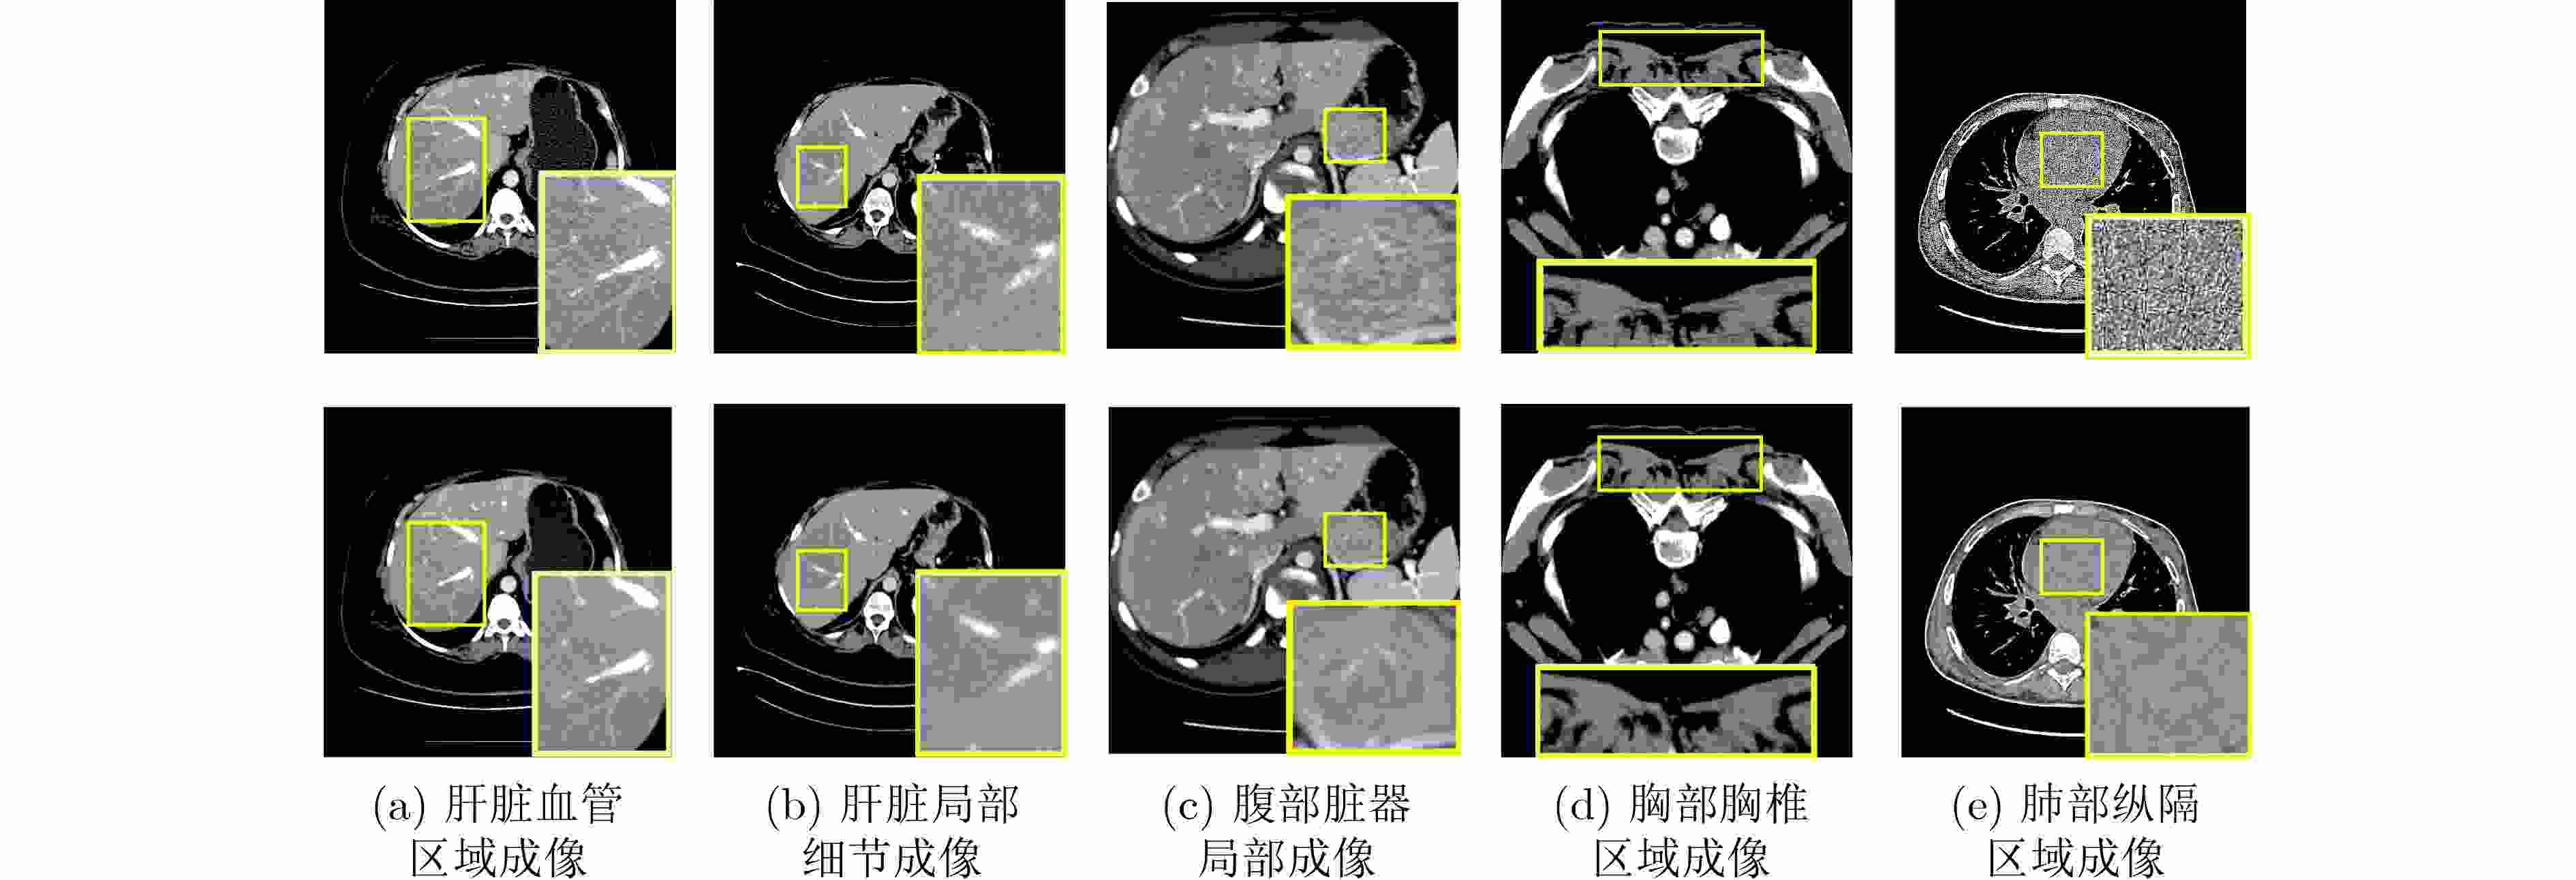

因果推理引导的KAN注意力脑肿瘤分类框架

樊亚文, 王翔, 岳震, 俞晓帆

当前状态:  doi: 10.11999/JEIT250865

[摘要](15) [HTML全文](3) [PDF 3050KB](2)

摘要:

脑肿瘤分类是医学影像分析中的关键任务,但现有深度学习方法在应对扫描参数差异、解剖位置偏移等因素时仍面临特征混淆问题,且难以建模肿瘤异质性引发的复杂非线性关系。针对这一挑战,本文提出一种因果推理引导的KAN注意力分类框架。首先,基于CLIP模型进行无监督特征提取,捕捉MRI数据中的高层语义特征;其次,基于K-means聚类设计混淆均衡度指标,筛选混淆因子图像。并设计因果干预机制,显式引入混淆样本,同时提出因果增强的损失函数以优化模型的判别能力;最后,在预训练ResNet主干网中引入KAN注意力模块,强化模型对肿瘤局部坏死区与强化边缘的非线性关联建模能力。实验表明,所提出的方法在脑肿瘤分类任务中优于传统CNN与Transformer模型,验证了其在判别能力和鲁棒性方面的优势。本研究为医学影像的因果推理与高阶非线性建模提供了新的技术路径。